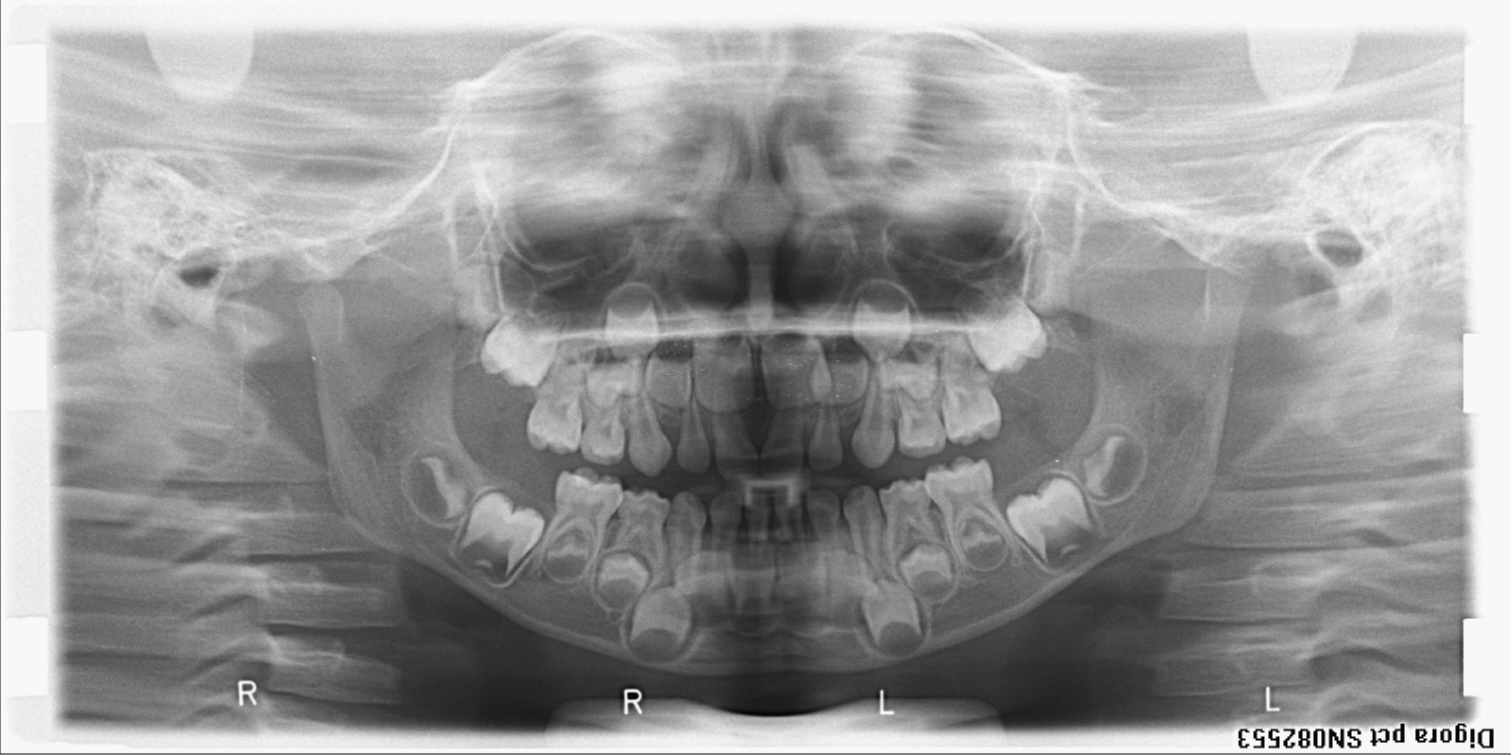

bilan des radiographies début et fin de traitement